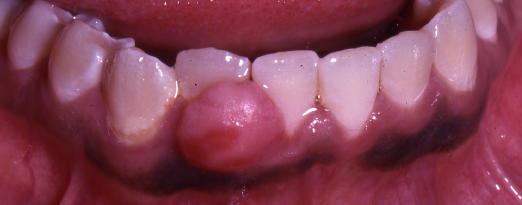

pyogenic granuloma

a common non-neoplastic proliferation of granulation tissue

a misnomer (not pyogenic, not granuloma)

response to local irritation or trauma

usually ulcerated

gingiva is the most common site

common during pregnancy

easily bleeds

pyogenic granuloma treatment

conservative surgical excision with removal of any local factors

lesions associated with pregnancy may spontaneously regress postpartum

recurrences occur due to remaining local factors (calculus)